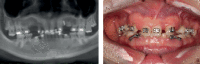

The guided bone regeneration (GBR) technique has been used to achieve optimal bone volume augmentation and allow dental implant placement in atrophic maxilla and mandible, with predictable results and high survival rates. The use of bone substitutes has reduced the necessity of autogenous bone grafts, reducing the morbidity at the donor areas and thus improving the patients' satisfaction and comfort. This clinical case report shows a clinical and histological evaluation of the bone tissue behavior, in a case that required the horizontal augmentation of the alveolar ridge, with the use of xenograft biomaterial and further dental implant placement. After six months of healing time, six implants were placed, and a bone biopsy was done. The histological analysis depicted some fragments of the xenograft bone graft, integrated with the new-formed bone tissue.